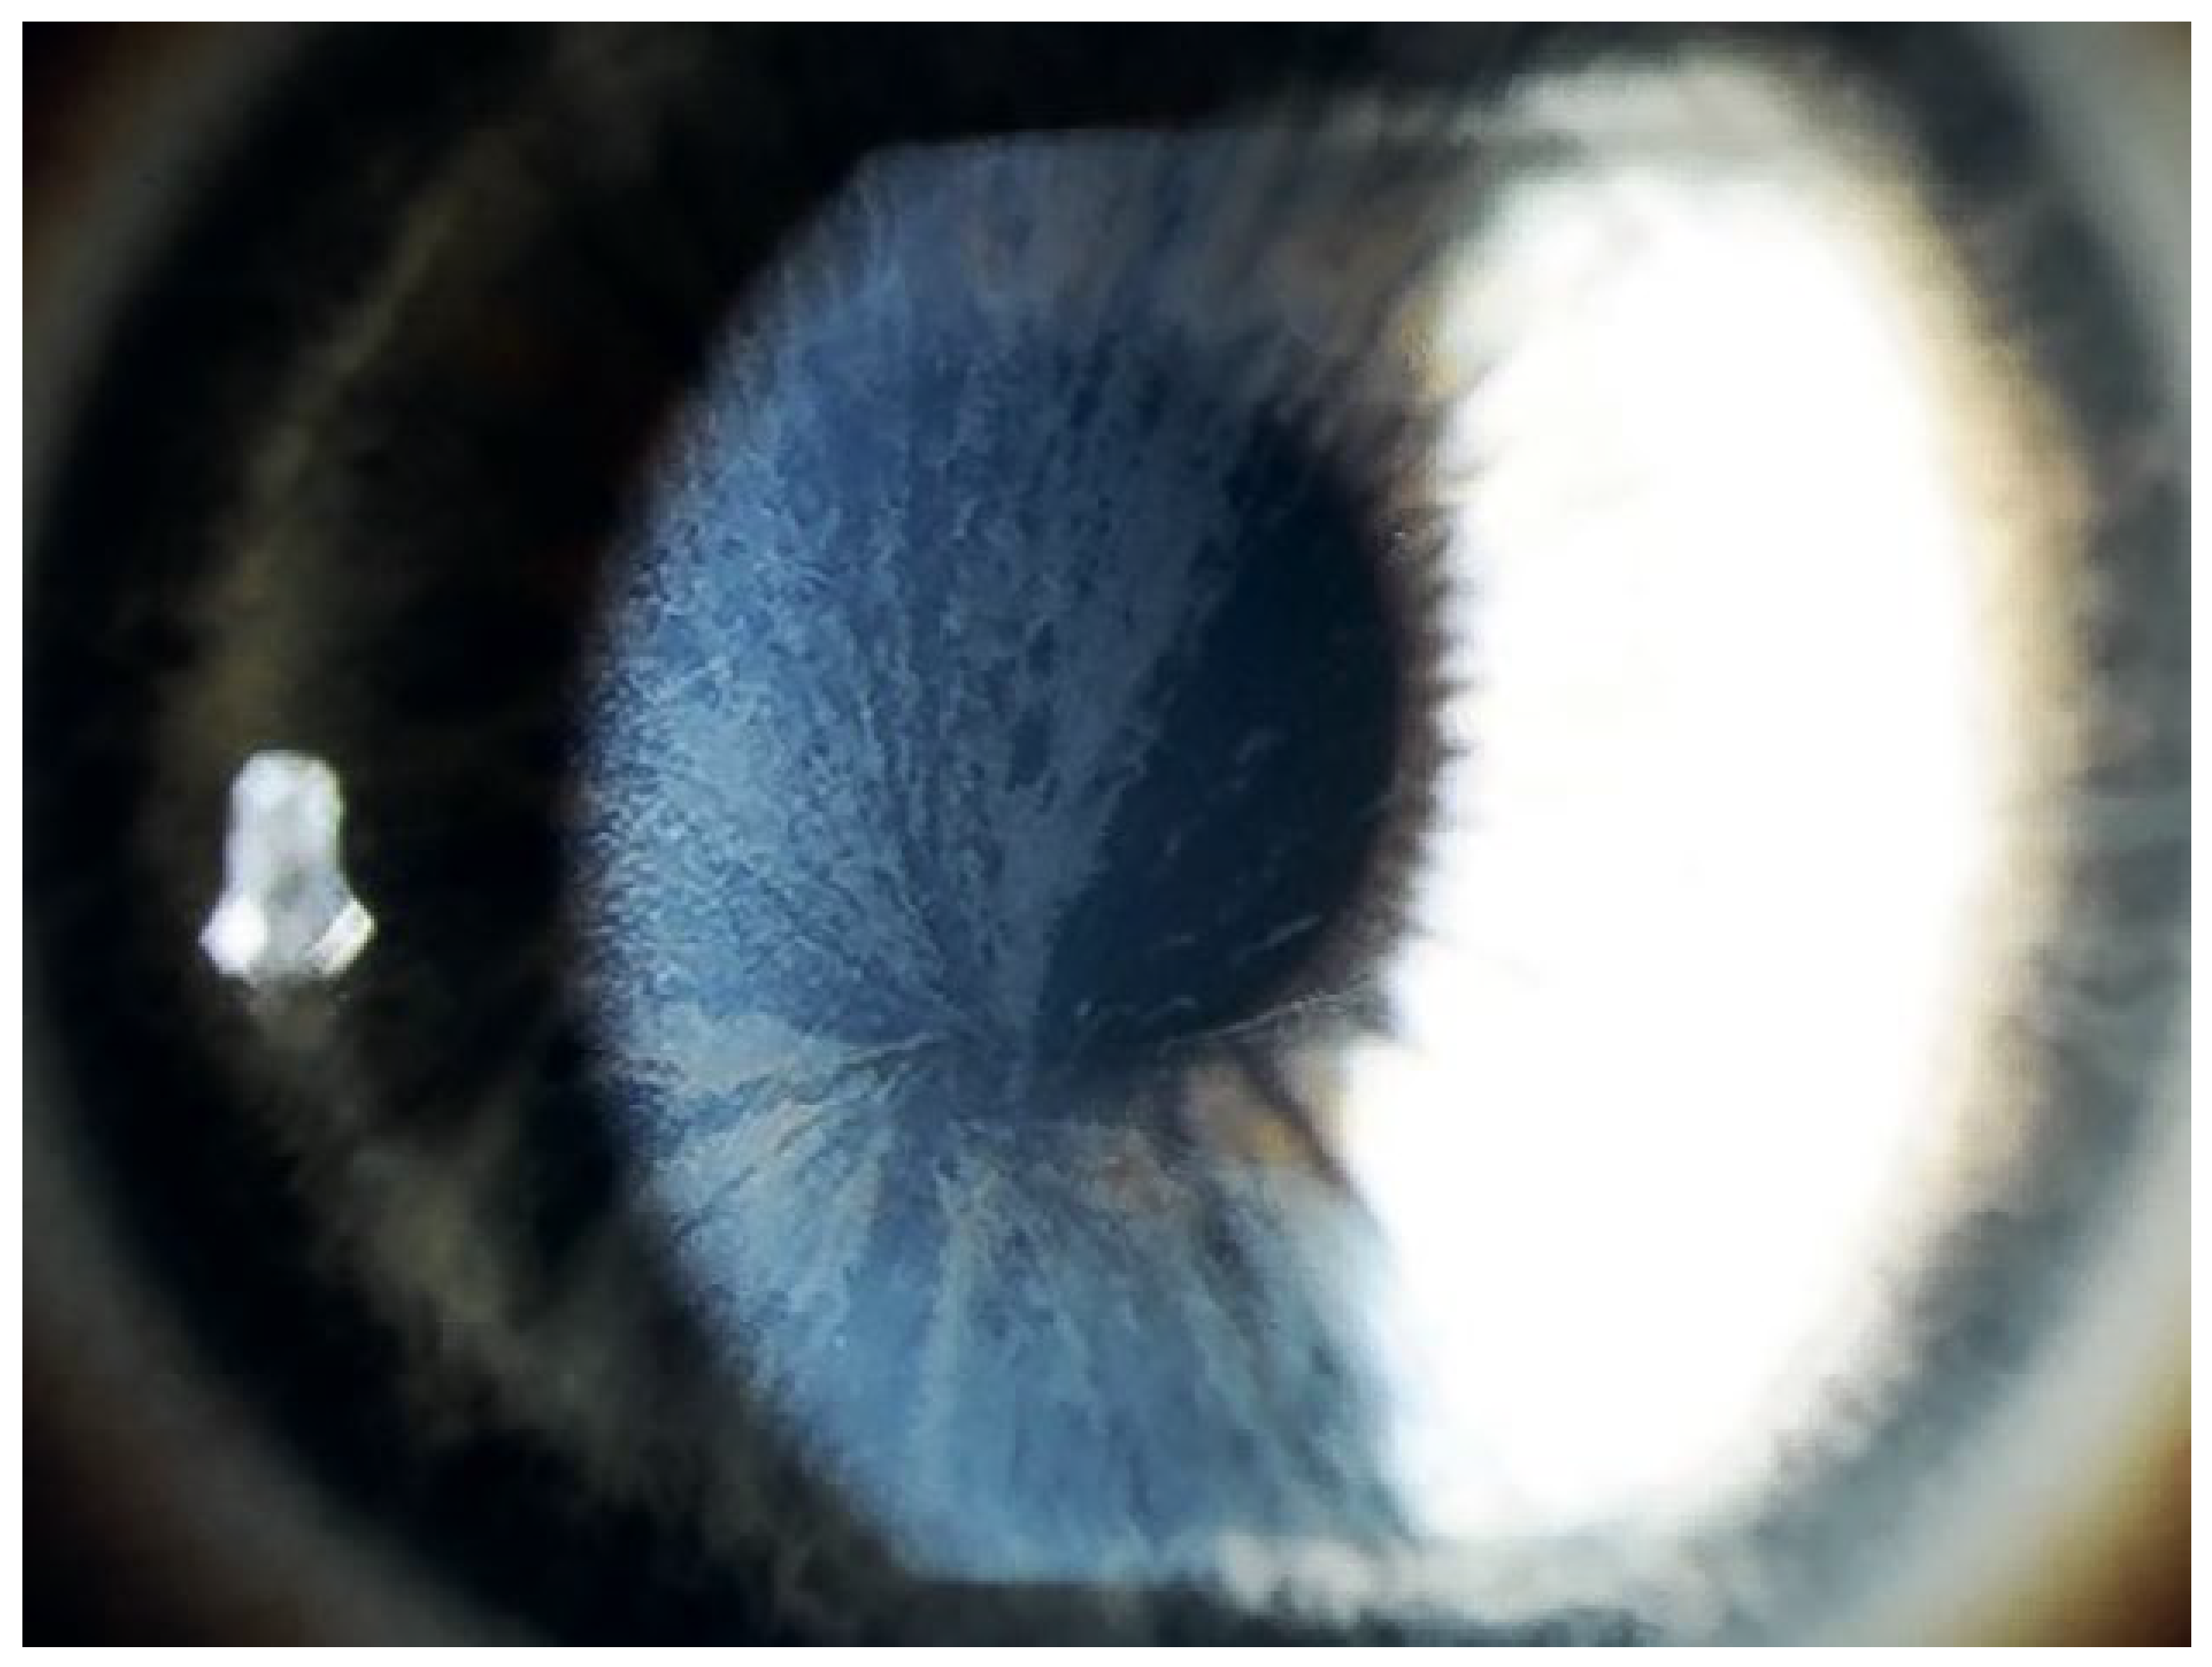

Welche anderen Organe sind betroffen?